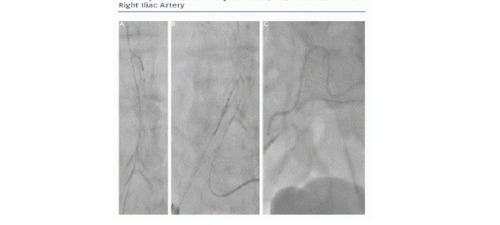

Some operators routinely advance a peripheral balloon in the external or common iliac artery from the contralateral access and inate it when retrieving the sheath and knotting the sutures - the so-called crossover balloon occlusion technique. This approach permits bleeding control and offers a bloodless eld for percutaneous or surgical repair if needed.9,13 In our experience, the need to inate a balloon to achieve haemostasis is rarely needed and we therefore do not use it prophylactically. However, we strongly advise having a diagnostic catheter in place in the external iliac artery using a contralateral approach. This can be easily done by advancing a 6 Fr internal mammary artery catheter over a 0.035" wire (usually a stiff Terumo wire, Terumo Inc, Japan). If the aortic bifurcation is narrow-angled and it is not possible to easily advance a wire into the contralateral limb, we advise snaring it (e.g. with EN Snare® Endovascular Snare System [Merit Medical Systems, South Jordan, Utah, US]) from the large bore introducer site. This technique may be the only way to 'secure' the contralateral limb in challenging cases (see Figure 2). From the 6 Fr mammary, an angiogram is performed to document complete haemostasis at the Prostar site (see Figure 3).

Crossover Final Angiography

It is essential to perform a nal angiography of the vascular access by a crossover approach to verify the haemostasis and to exclude local complications such as dissection or vessel occlusion. Small leaks are not seen from the skin and they may contribute to the formation of a false aneurysm or become the source of delayed major bleeding. If small vascular leakages are seen, prolonged manual compression is usually effective in sealing the leak and a nal angiographic check is required to conrm the sealing. Large leaks or tears often require covered stenting or surgical intervention. In this setting, proximal balloon occlusion is a valuable bridge to endovascular or surgical repair.